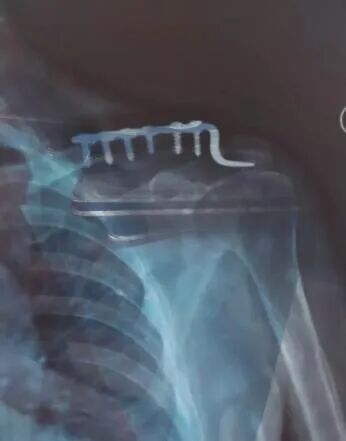

有些部位皮包骨头,比如肘关节、锁骨、踝关节、膝关节前方等,这里的骨折,放上钢板之后,皮肤下面就是钢板,很容易在日后发生问题。比如膝盖前方髌骨的内固定可能会影响到跪地的动作,而肘关节后方的钢板可能会在弯曲胳膊肘时顶到皮肤。所以这些皮包骨头部位的钢板如果已经产生了疼痛的症状,就要取出。就算现在还没有症状,但是预计在患者的预期生命里或者结合患者的自身工作性质可能以后会造成影响的,也应该取出。这种情况说明此处的软组织已经出现问题,很可能已经感染或者即将出现感染,如果X片显示骨折已经愈合,最好立即取出钢板,以便很好的控制感染。如果出现因为钢板影响到了关节的活动,应该尽早取出。否则时间久了,关节僵硬、增生、退变都会随之而来。

有些部位的骨头是形象外观的组成部分,比如锁骨,比如手掌骨指骨,比如踝关节,对于瘦的人来说,这些部位放上钢板后会凸出钢板的形状,可能会对某些爱美人士带来自信心和自我认同方面的影响。所以即使没什么疼痛症状,不妨取之。

这些部位的钢板大多紧邻血管神经,解剖复杂,再加上已经手术过一次,骨折部位周围的肌肉软组织满是瘢痕,解剖层次还不如刚骨折时候清晰。手术损伤血管神经的风险比放钢板时候还要大,所以尽量不要取。

取钢板前应认真清理钢板周围的骨痂,仔细核对螺丝钉的数目,务必全部取出; 钢板无明显骨痂包裹,螺丝钉全部取完后钢板仍难取出时要注意钢板原来没有上螺丝钉的钉孔部位,最易被瘢痕缠绕包裹,切断缠绕钢板的斑痕组织,即可取下钢板。